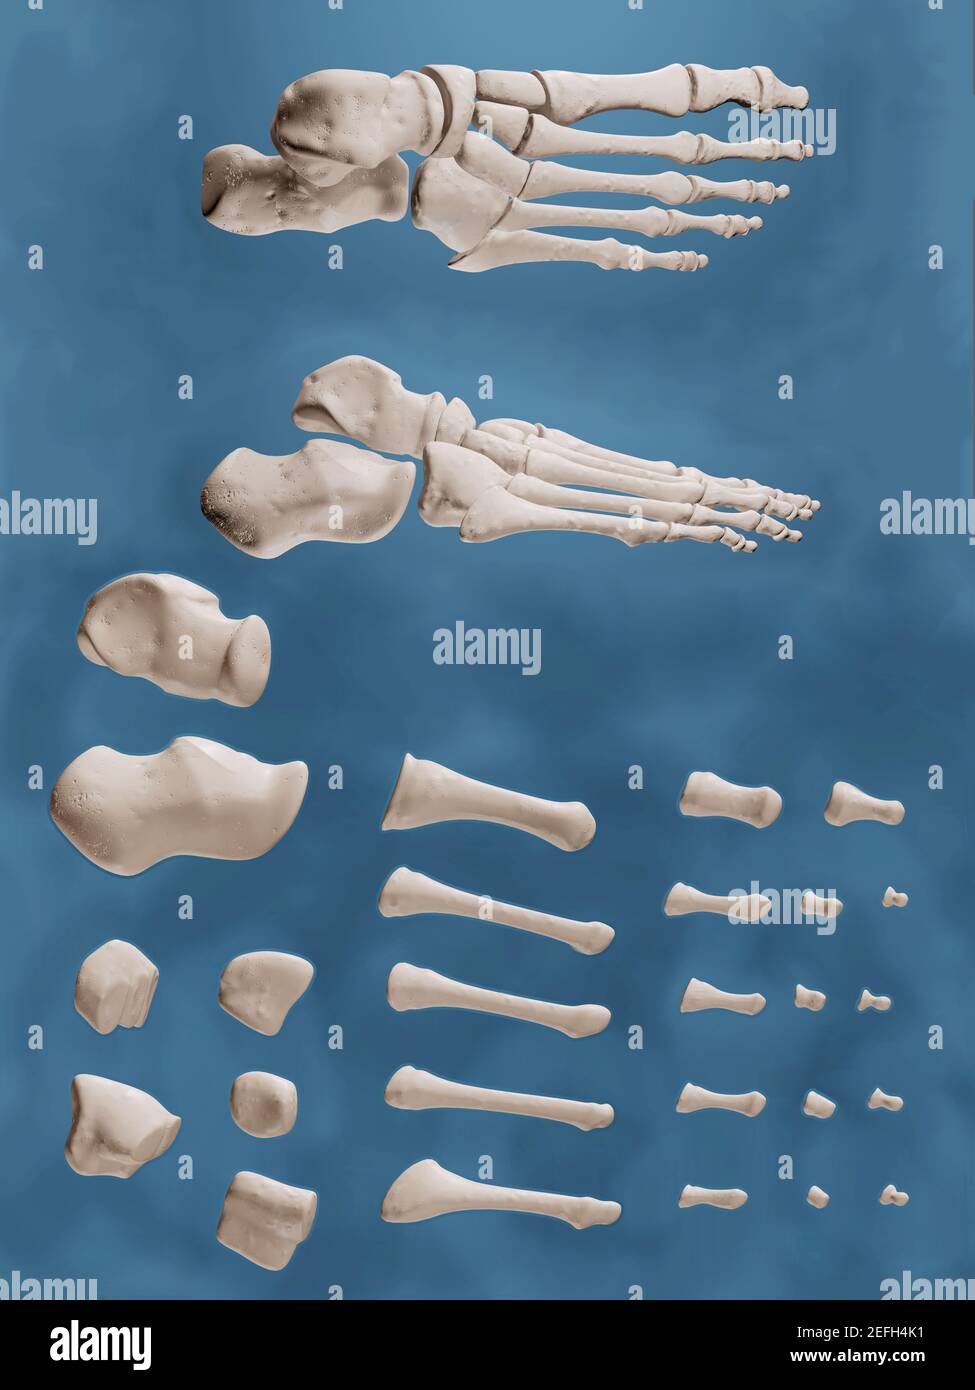

RF2EFH4NT–Affiche prête pour la salle de classe montrant les os du pied dans des vues anatomiques et éclatées.